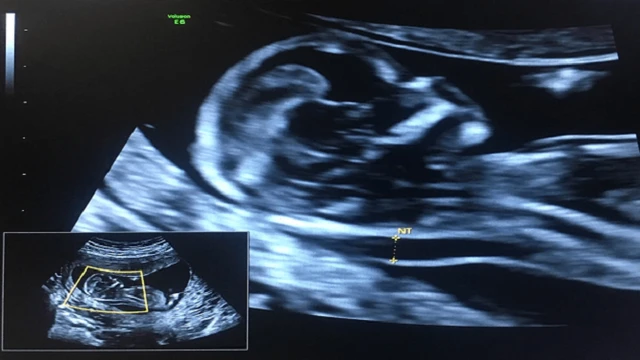

Mang thai tuần 15 là thời điểm nhiều mẹ bầu bắt đầu cảm thấy yên tâm hơn vì đã đi qua giai đoạn ốm nghén của 3 tháng đầu. Tuy nhiên, không ít người vẫn băn khoăn thai 15 tuần đã an toàn chưa, thai nhi phát triển thế nào, cơ thể mẹ thay đổi ra sao và cần lưu ý gì để bảo vệ sức khỏe trong giai đoạn này.

Thai 16 tuần nặng bao nhiêu là thắc mắc của nhiều mẹ bầu khi bước vào giai đoạn giữa tam cá nguyệt thứ hai. Lúc này, em bé đang phát triển nhanh về chiều dài, cân nặng và các cơ quan quan trọng. Việc theo dõi chỉ số thai giúp mẹ hiểu rõ sự tăng trưởng của con theo từng tuần.